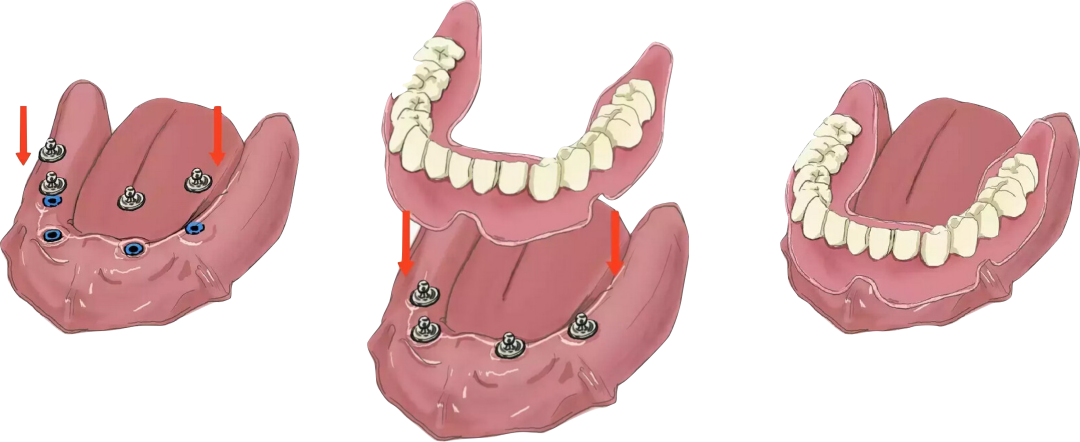

种植覆盖义齿修复:

价格介于全口种植与全口义齿之间。

在口腔内,如果只有一两处骨头条件好的地方,可以少种几颗植体,然后再做一个活动的附件,把义齿覆盖在上面。这种方式采用种植和黏膜联合支持、固位修复,义齿可以自行摘戴,需要手术植入植体,价格也比较高。